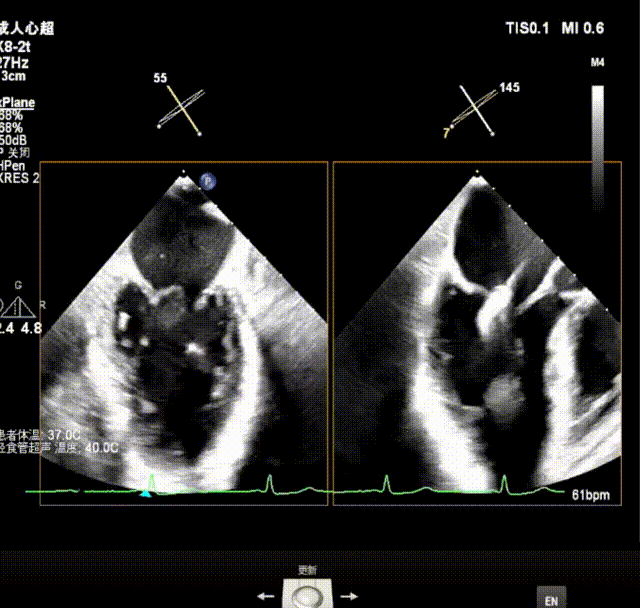

术中及术后即刻超声评估

测量穿刺点距离二尖瓣环的位置,测量为4.35cm;沿着导丝置入可调弯导引导管,使其穿出穿刺点2cm左右

经导管瓣膜夹输送系统进入左房,进行打弯调整使瓣膜夹朝向二尖瓣

瓣上M/L和A/P调整瓣膜夹,在X-plane进行超声确认(视频),进行弹道路径检查;

3D指示下调整瓣膜夹朝向病变区域

关闭瓣膜夹在超声指引下推进到左心室;打开瓣膜夹至120°,超声下抓捕瓣叶。

确定瓣膜夹与病变区域垂直后,放下夹片;超声确认前叶后叶都夹合充分,3D检查瓣膜夹位置.

瓣膜夹释放前评估发现返流改善明显,但是P1脱垂外侧仍有少量返流,综合考虑决定再植入一枚长宽瓣膜夹;

超声测量前瓣夹持长度0.91cm,后瓣夹持长度约1.14cm

第二枚瓣膜夹紧挨着第一枚瓣膜夹;夹合P2偏P1区脱垂,分担张力,稳定释放瓣膜夹,返流消失。

释放后平均压差2mmHg,瓣口面积可,超声PW显示左肺静脉收缩期逆流消失.

最终释放用多普勒超声评估返流程度,返流情况改善明显,术后仅残留少量反流( MR 1+),术后跨瓣压差5mmHg,无瓣口狭窄;肺静脉逆流情况消失,血流动力学显著改善;3D超声下,瓣膜组织桥稳定。术后即刻评估,返流几乎消失,手术成功。